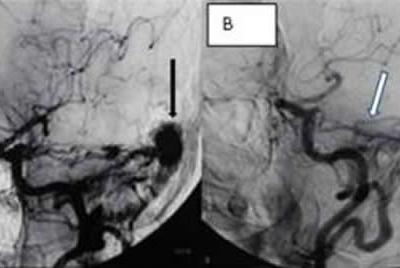

61岁男性患者行右枕部硬脑膜动静脉瘘手术前(A)和10年后(B)的血管造影。白箭头...